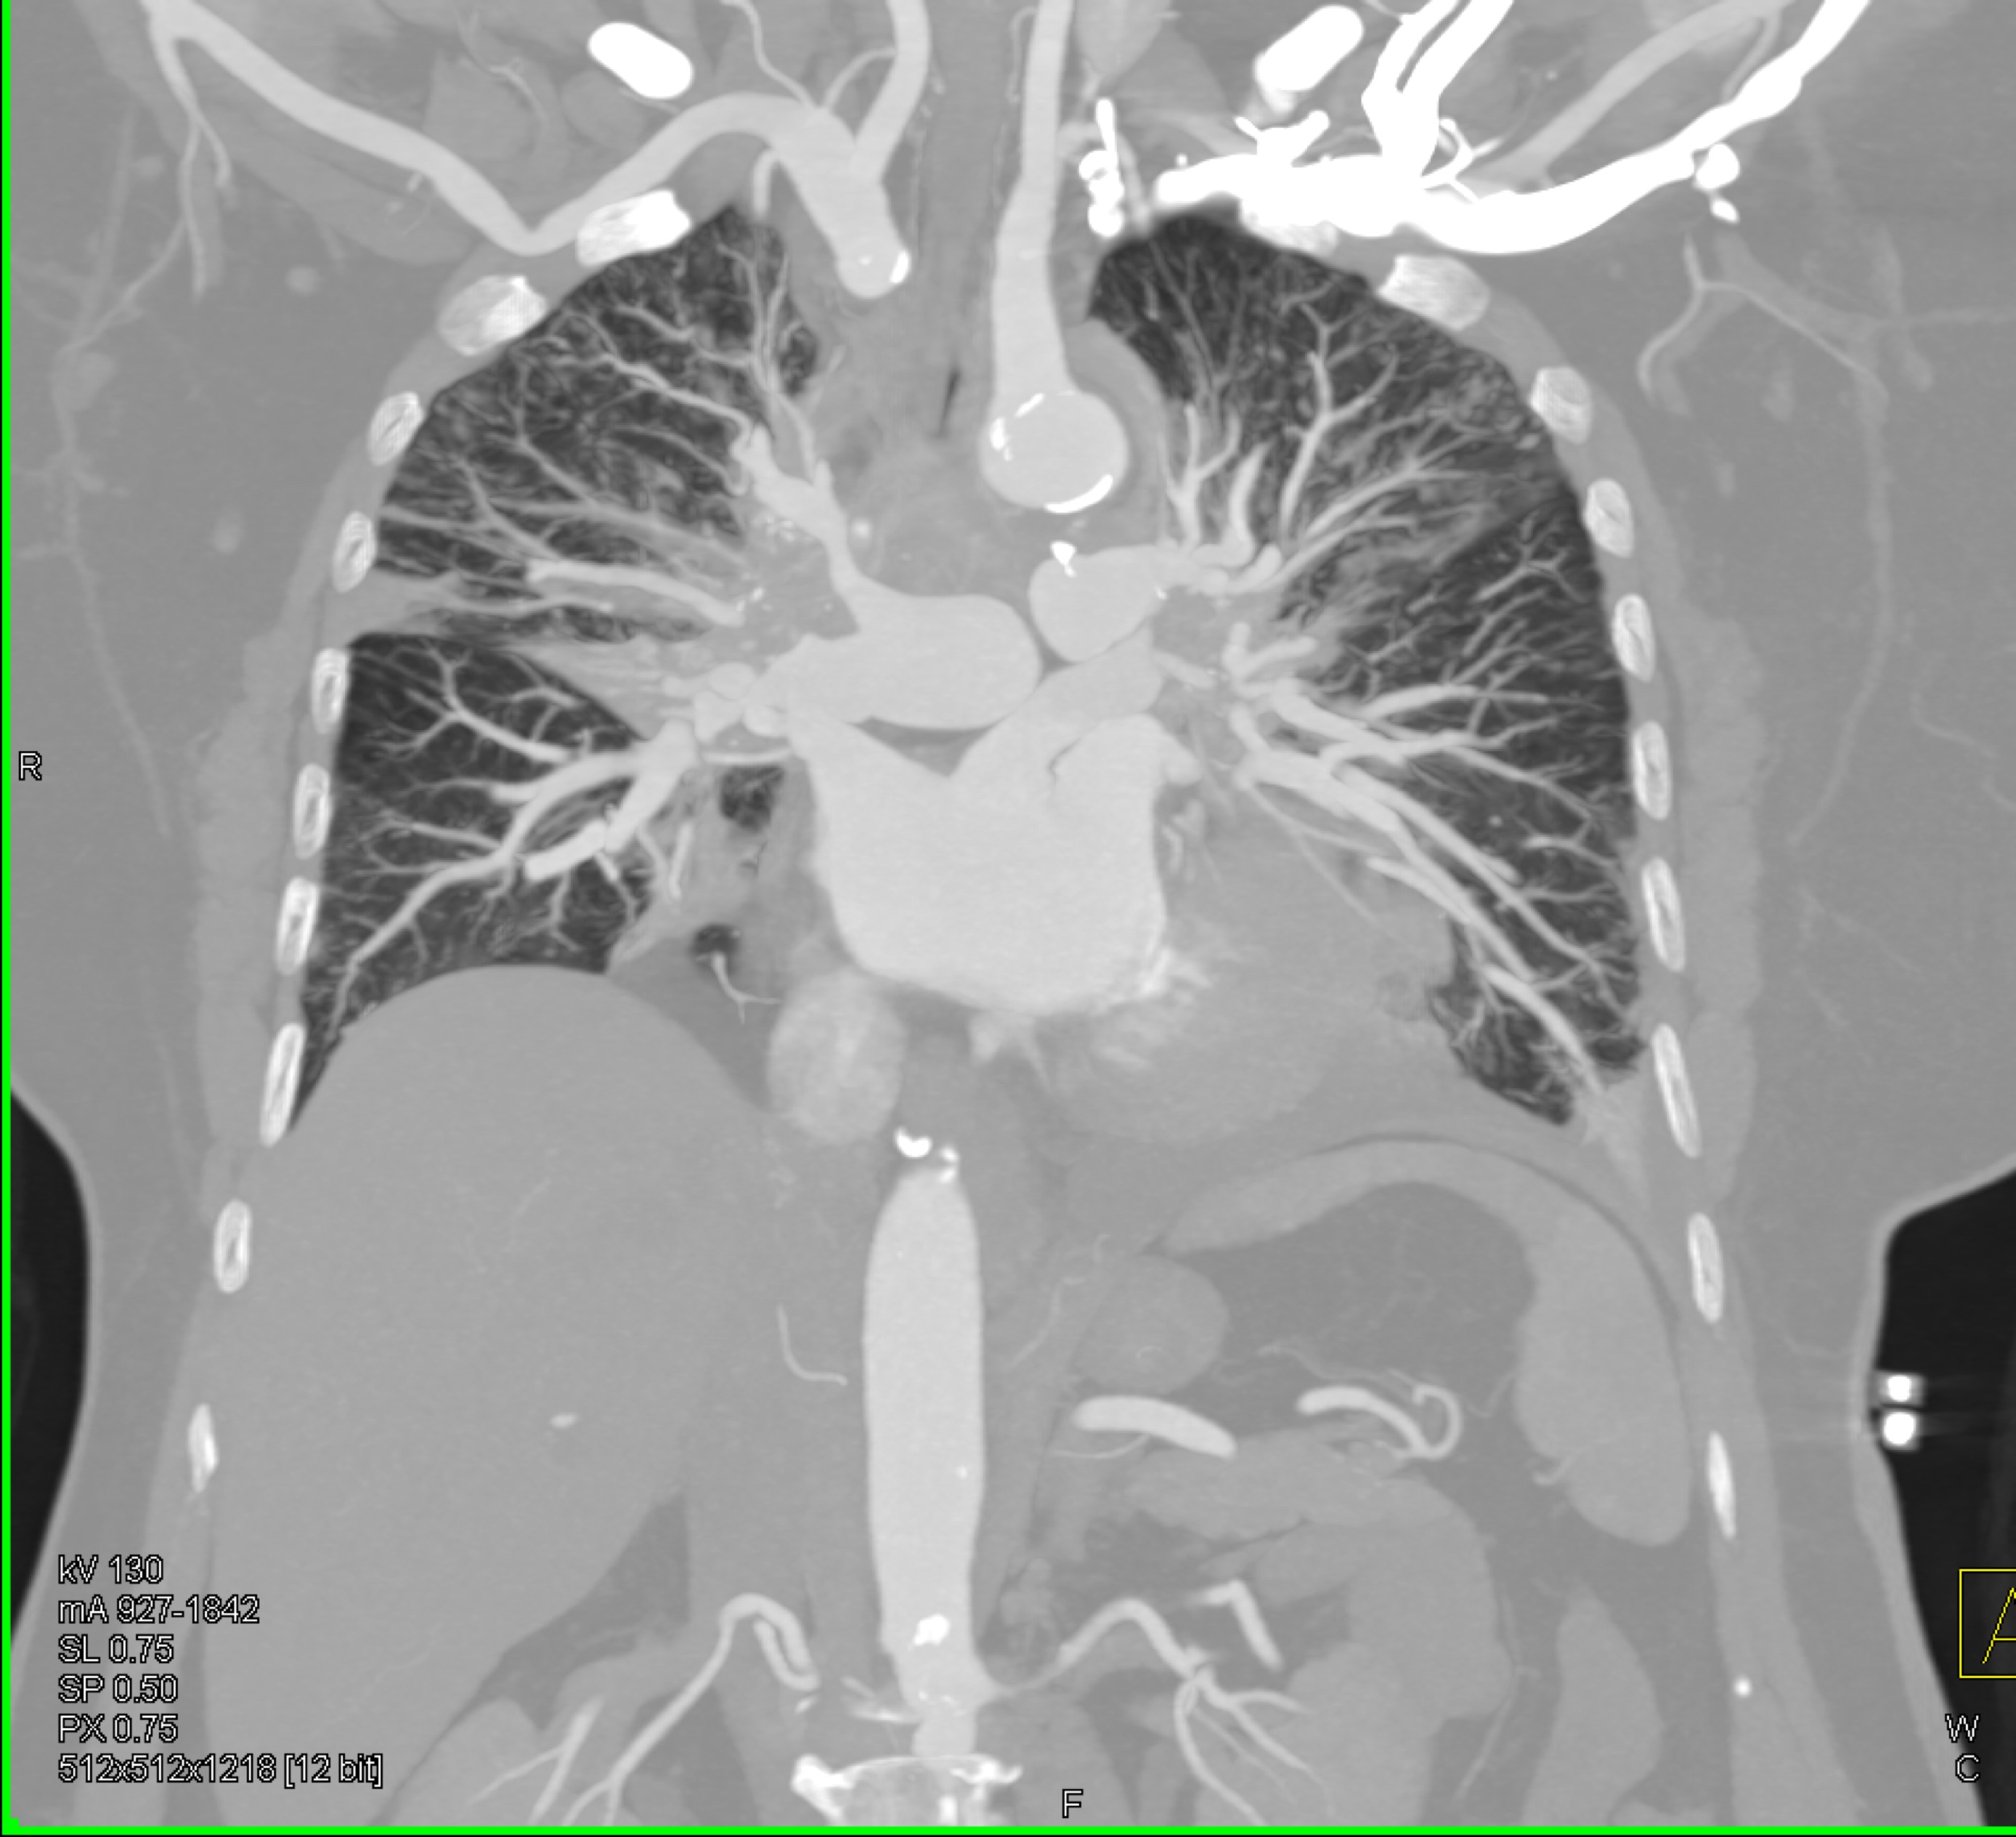

4) The least likely diagnosis in this case is?

fibrosing mediastinitis

sarcoidosis

lymphoma

COVID pneumonia